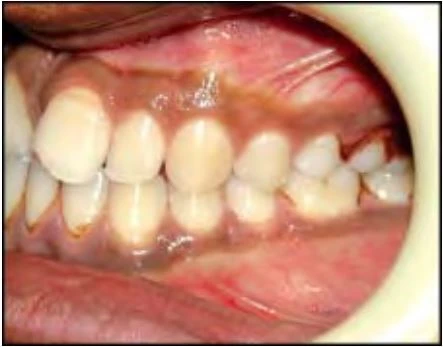

2.3 SAI KHỚP CẮN THEO MẶT PHẲNG NGANG

Trường hợp này bao gồm nhiều kiểu cắn chéo khác nhau. Thông thường các răng hàm trên nằm về phía ngoài so với các răng hàm dưới, nhưng đôi khi do cung răng hẹp hoặc vì một số lý do khác mà tương quan này bị xáo trộn. Chẳng hạn một hoặc nhiều răng hàm trên nằm về phía trong so với các răng hàm dưới, tình trạng này khác nhau về mức độ, vị trí và số lượng răng liên quan.